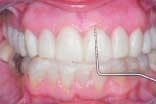

The assistant retracts the lips for the next set of images. These two images are the arches in occlusion and slightly open. The image of the teeth in occlusion gives us information on overbite, overjet, cross bites, gingival recession, Golden Proportion, Shimbashi number, and exostosis. A periodontal probe can be placed on the central incisor as a reference for measurement. This view can be used to analyze and diagnose Golden Proportion on a printed view with a ruler and pen or with measurement tools found in many software applications.